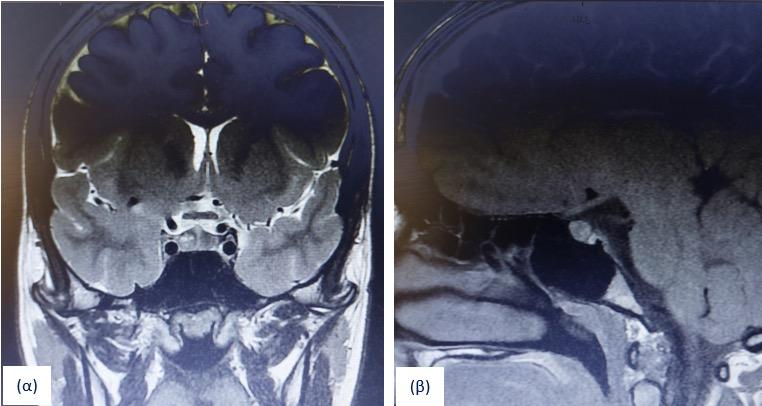

Microprolactinoma presenting as galactorrhea in an adolescent: diagnostic and therapeutic approach

Background: Prolactinomas account for more than 50% of anterior pituitary tumors, are usually benign and rare in adolescence (1-10/100,000). Clinically, they present with galactorrhea, delayed puberty, menstrual disturbances and infertility. Diagnosis relies on measurement of prolactin (PRL) levels and pituitary MRI with contrast. First-line treatment is cabergoline.

Methods: We report a 15-year-old girl with a 7-month history of galactorrhea. Menarche occurred at 1110/12 years, with regular menses lasting 4–6 days every 25–28 days. Physical examination was unremarkable [Tanner stage IV for axillae-breasts-pubic area, Weight=55.8 kg(50–85th pc), Height=161.3 cm(50th pc)], except for milky nipple discharge.

Nikolaos Siskas

Results: Extensive laboratory evaluation was normal, except for elevated morning levels in two occasions PRL: 138ng/ml (0 min), 132ng/ml (20 min) and repeat 110.5ng/ml (ref. 1.8–29.2ng/ml), confirming hyperprolactinemia. Nipple discharge cytology was negative. Pituitary MRI revealed a hypovascular lesion measuring 6×5×7 mm, consistent with adenoma. The diagnosis of microprolactinoma was established and cabergoline was initiated at 0.5 mg/week. After one month, PRL decreased but remained above normal, while galactorrhea persisted. Consequently, the cabergoline was escalated to 0.5mg twice weekly maintained to date. Over a two-year follow-up period, patient remained asymptomatic, with normal PRL levels and progressive reduction of the microprolactinoma on annual MRI scans. Conclusions: Galactorrhea in adolescence is abnormal requiring endocrinological evaluation. Elevated PRL levels and MRI findings support the diagnosis of prolactinoma. Cabergoline is effective and well-tolerated. Long-term monitoring (PRL, MRI, clinical) is necessary to detect recurrence and assess remission. Prognosis is excellent, especially in microprolactinomas with good compliance.